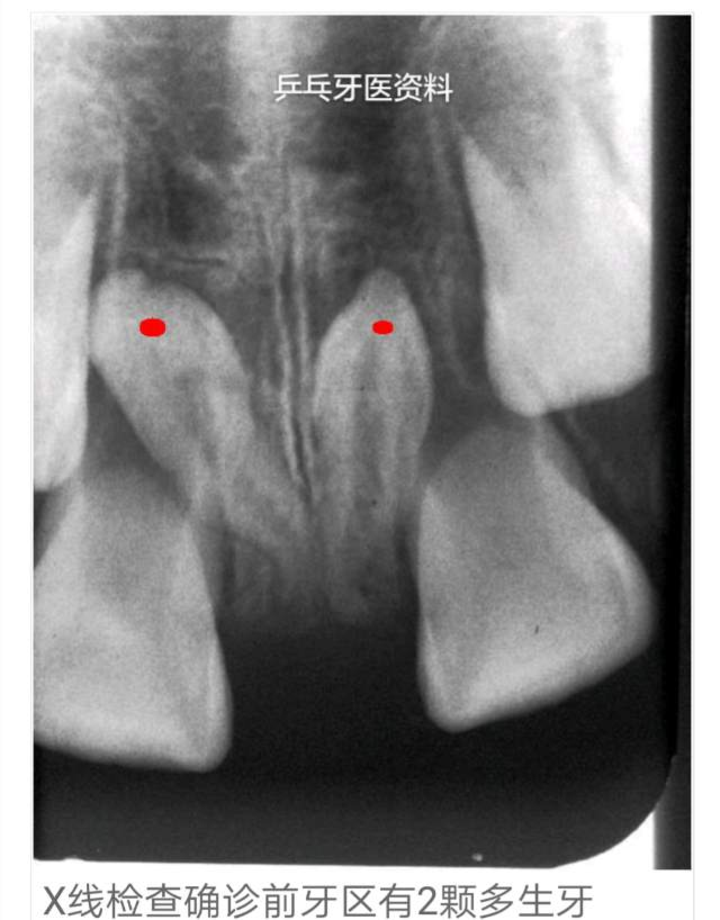

1.门牙间隙过大